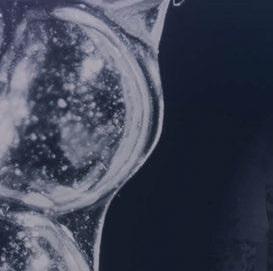

Para ilustrar el proceso, presentamos el caso de una mujer joven diagnosticada de carcinoma adenoide quístico en la región posterior del hemipaladar izquierdo (Figuras 1 y 2). El procedimiento quirúrgico realizado fue una

Figura 1. Imagen preoperatoria de la paciente.

Figura 2. Carcinoma adenoide quístico en región posterior del hemimaxilar izquierdo.